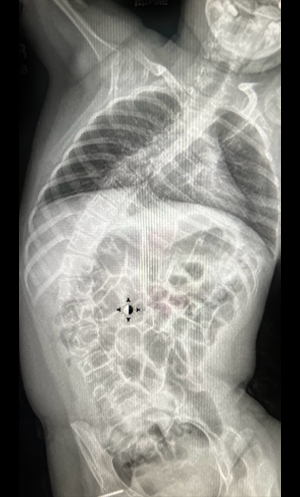

Gallery : Before - After

• Scoliosis surgery with small incisions using flexible correction technology (VBT) and growth-preserving techniques such as remotely controlled magnetic growing rods

• Kyphosis correction surgery

• Corrective spine surgeries, complex spine surgeries, and revision of failed surgeries